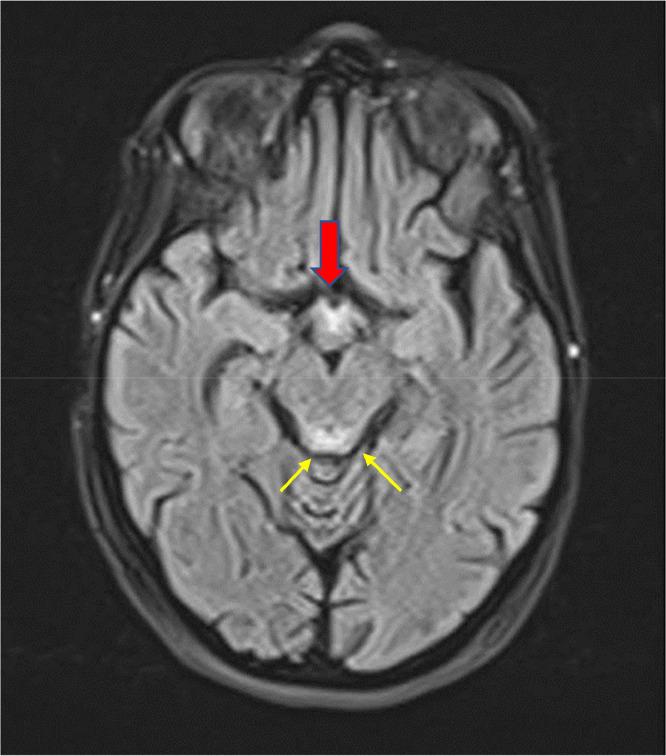

脑部磁共振成像:诊断孕妇盖耶-韦尼克脑病的一种安全且特异的工具:病例报告

Brain MRI: A safe and a specific tool in the diagnosis of Gayet Wernicke's encephalopathy in pregnant women: Case report.

Gayet-Wernicke encephalopathy (GWE) is a neuropsychiatric syndrome due to Vitamin B1 (thiamine) deficiency, fatal in 30% of cases and preventable if treatment is initiated early, characterized by the classic triad of encephalopathy, ocular involvement: ophthalmoplegia and/or nystagmus and ataxia. GWE is mainly observed in alcoholics, but can also appear in any state of malnutrition. In obstetrics, hyperemesis gravidarum can be complicated by GWE due to low thiamine stores and increased thiamine requirements. We report a case of Gayet-Wernicke encephalopathy complicating incoercible vomiting in a pregnant woman.

摘要

盖耶-韦尼克脑病(GWE)是一种由于维生素B1(硫胺素)缺乏引起的神经精神综合征,30%的病例会致死,若早期开始治疗则可预防,其特征为脑病、眼部受累(眼肌麻痹和/或眼球震颤)和共济失调这一经典三联征。GWE主要见于酗酒者,但也可出现在任何营养不良状态下。在产科,妊娠剧吐可因硫胺素储备不足和硫胺素需求增加而并发GWE。我们报告一例孕妇出现无法控制的呕吐并并发盖耶-韦尼克脑病的病例。